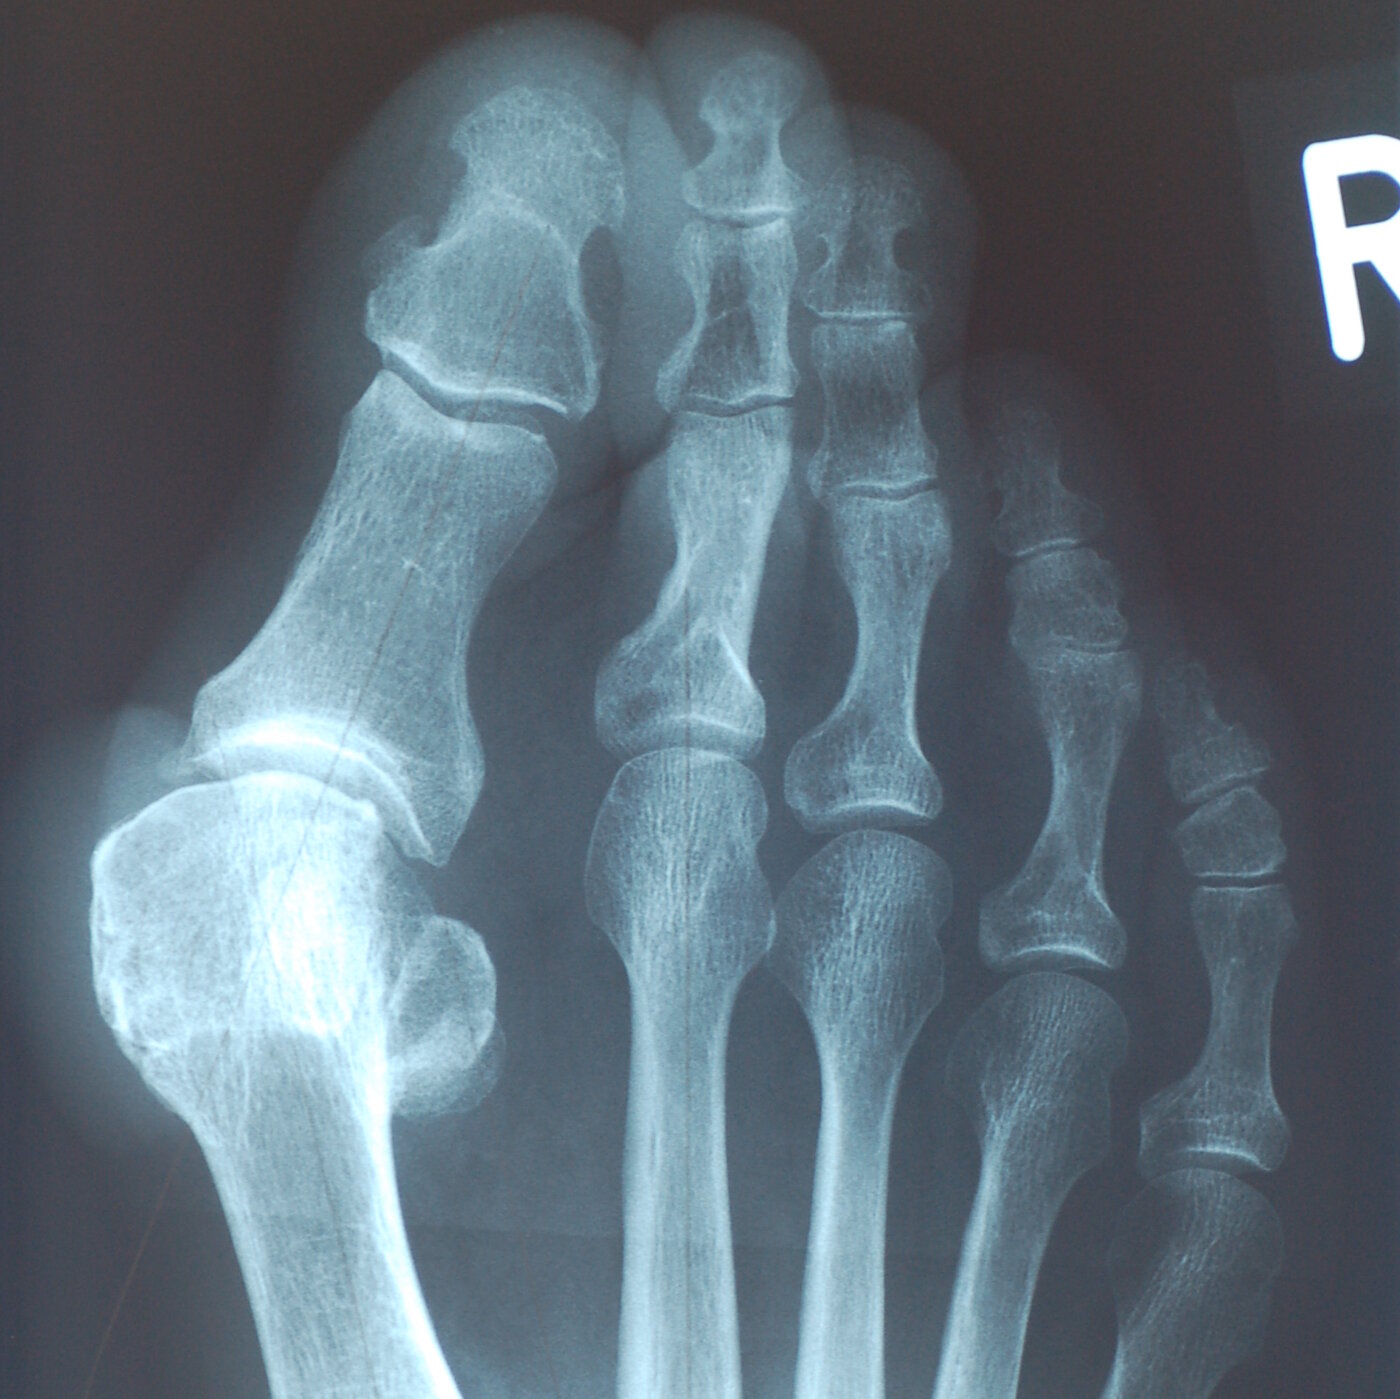

Unter Hallux valgus (auch Großzehenballen genannt) versteht man eine Abweichung der Großzehe nach kleinzehenwärts. Nicht eine Knochenanlagerung sondern das herausgetretene Mittelfußköpfchen bildet den „Ballen“. Neben erblicher Vorbelastung begünstigt enges Schuhwerk die Fehlstellung.